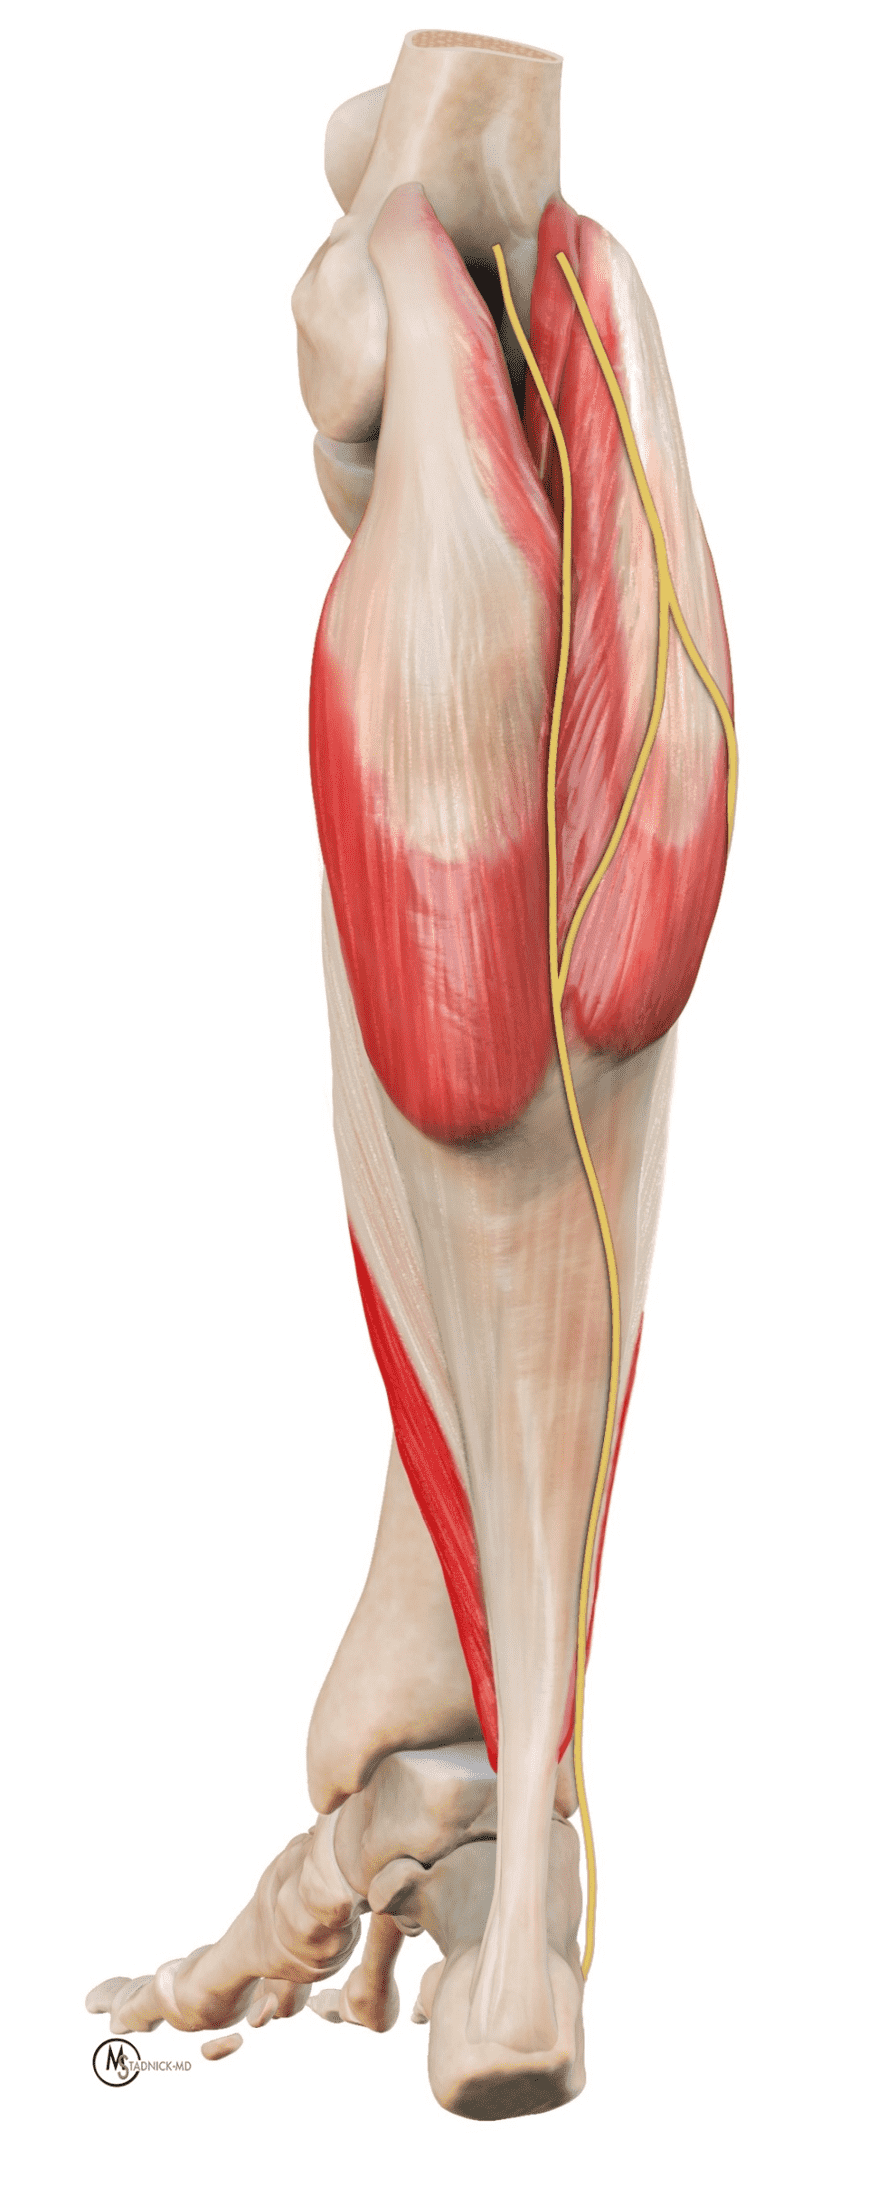

The retrocalcaneal bursa sits between posterior calcaneal fibrocartilage and the distal tendon. The normal bursa measures <7 mm craniocaudal, <2 mm AP, and <11 mm transverse. Kager’s fat pad is mobile and can invaginate into the bursa during plantar flexion, reducing friction.5, 6 The plantaris tendon usually courses medial to the Achilles near the musculotendinous junction with variable insertions; an accessory soleus muscle and tendon located anteromedial to the Achilles is a common normal variant and its presence may coexist with Achilles tendinosis. 8, 11,15,16 The sural nerve, a sensory nerve that innervates the skin in the distal posterolateral leg, courses along the dorsal surface of the distal gastrocnemius muscle bellies and the proximal Achilles tendon, and then along the lateral margin of the mid and distal tendon before entering the hindfoot posterior to the peroneal tendons (Figure 3A).17

Figure 3: Illustrations of the normal anatomy related to the Achilles tendon. (3A) A posterior projection shows the tendon forming as a confluence of the gastrocnemius heads (medial and lateral) and the soleus. The sural nerve courses along the superficial surface of the proximal Achilles tendon and the lateral margin of the mid and distal tendon; the nerve is at risk of iatrogenic injury during percutaneous tendon repairs. (3B) Renditions of the Achilles insertion. The Achilles tendon components (medial gastrocnemius-blue, lateral gastrocnemius-red, soleus- green) spiral proximal to their insertions, with the retrocalcaneal bursa (yellow) located between the tendon and posterosuperior calcaneus. The lower drawing shows the respective calcaneal facets (superficial-yellow, medial aspect of the middle facet-green, lateral aspect of the middle facet-red, inferior facet-blue).